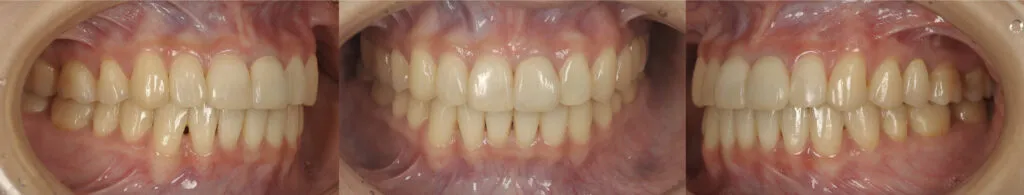

症例3

- 主訴

- 歯が揺れている。全体的な治療を希望

- 治療内容

- インプラント治療、セラミックによる補綴治療

- 治療費

- 450万

- 治療期間

- 1年6ヶ月

- 通院回数

- 50回

- 想定されたリスク

- 将来的な二次カリエス、歯周病の悪化

- コメント

- 入れ歯を使用せずに、しっかり噛めるようになりたいという希望を達成することができました。

before

after